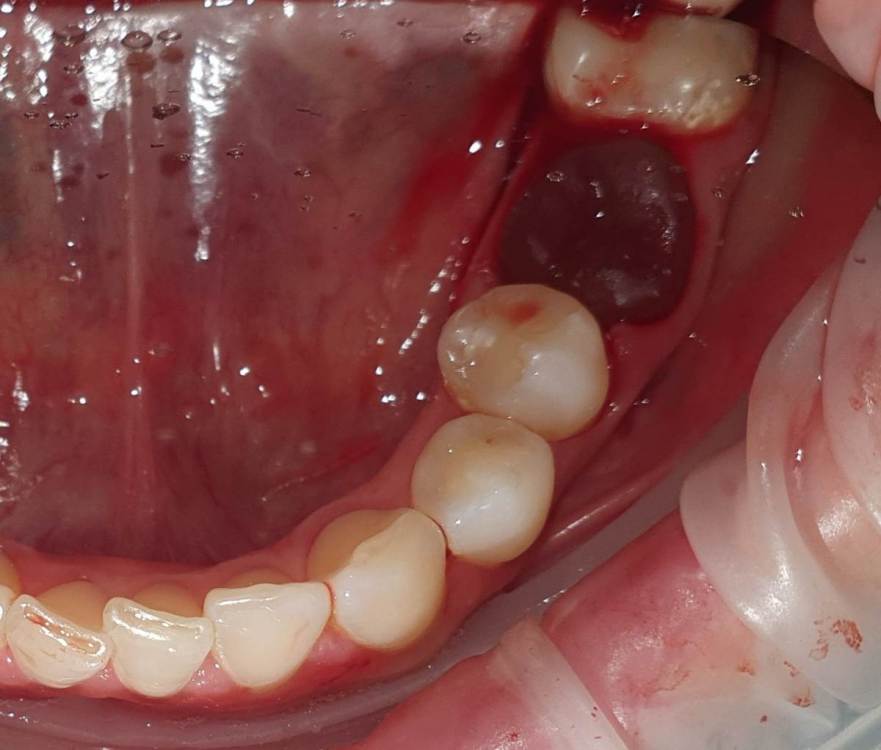

Dr.Deletle Опубликовано 22 июля, 2023 Поделиться Опубликовано 22 июля, 2023 (изменено) Этот кейс интересен тем, что у пересаживаемого 2.8 полностью сформированы корни. Пациент Н., 35лет, зуб 3.6 подлежит удалению по терапевтическим показаниям. Донором был выбран зуб 2.8. Фото №1, 2 - ситуация ДО на фото и срезе КЛКТ Фото №3 - планирование на реконструкции ОПТГ из КЛКТ Фото №4 - шаблон зуба 2.8 Фото №5, 6 - операция, удален 3.6, припасован шаблон, пересажен 2.8 (фиксирован швами и шиной к 3.7) Фото №7 - КТ сразу после пересадки Фото №8, 9 - депульпирование пересаженного 2.8 через 2 недели Фото №10 - снятие шины через 2нед после пересадки Фото № 11, 12, 13 - состояние в полости рта и на срезе КТ через год после пересадки, видно сформированное периодонтальное пространство, здоровая костная ткань, жалоб у пациента нет, полноценно жует как обычным зубом Изменено 22 июля, 2023 пользователем Dr.Deletle 4 3 Ссылка на комментарий